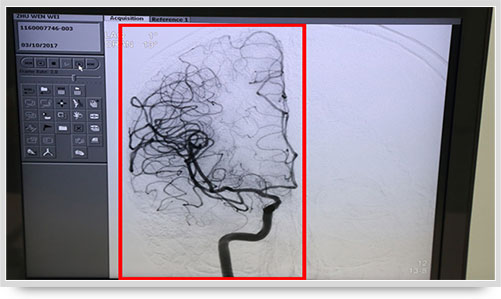

全脑血管造影术(DSA)是运用数字减影技术下进行的全脑血管摄片,因此又称数字减影血管造影。技术上一般采用局部麻醉,右侧股动脉穿刺、置管,再将一根造影管通过腹主动脉、主动脉弓,选择性进入左右颈内动脉和椎动脉后,分别造影,发现病灶后还应行三维血管造影。造影图像较以往所用的常规脑血管造影所显示的图像,更清晰和直观,一些精细的血管结构亦能显示出来,是目前国际上公认的血管性疾病诊断的“金标准”。

弓上造影、超选到颈内动脉、椎动脉......在数字减影技术下,注入显影剂后,导管经患者右侧股动脉在体内推进,由于股动脉离脑血管距离较远,中间“路程复杂”,对施术医生的要求非常之高。

同时,手术台前的液晶显示仪屏幕上清晰地现显出导管的路径,在李主任的操作下准确到达指定检查部位,各条血管的“庐山真面目”清晰可见。